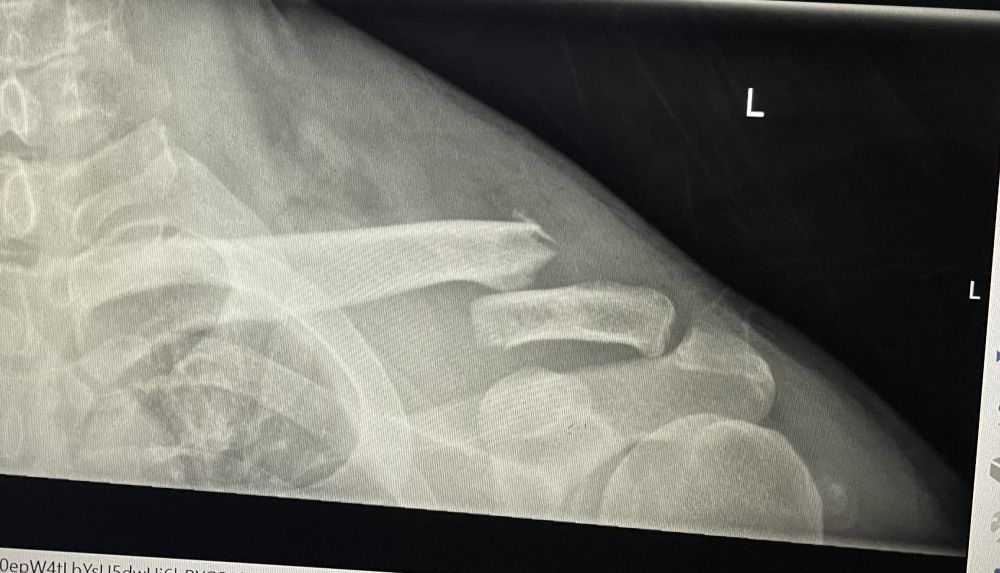

第二天,我在病床上接待了许多医生。其中印象比较深刻的是来自什么trama recovery的医生。他操着北美口音,分不清是美国还是加拿大的,双手插在裤兜里(从来没有见过医生如此),一边走一边上身左右摆动,似乎很逍遥,也很潇洒,一副都在我掌控之中的模样。身后跟着两位,一位可能是他的下手,另外的那位可能是见习医生。我们客套了两句,他说:你的伤势不严重,可以出院回家恢复。我本人思想一向比较积极,一听觉得如果可以回家休养,那说明伤势的确不严重,那我就回去恢复好了,何必耗在病床上呢!不过又一想,昨天半夜上洗手间,对着镜子,发现我左肩膀歪斜着,倒塌似的。于是问他:我可以看看片子吗?他说可以,拿出手机给我看我片子。

我一看,心想:你他妈安的什么心?这能自我恢复吗?于是问他:你说的恢复是什么意思呢?他说:恢复后,你左臂的活动范围回减少,两边的肩膀不对称了,一边低一些。边说边做示范。我心想:你个婊子,如果你,或你的家人同样状况,你会给同样的建议吗?于是我想:这样就让我出院,没门?